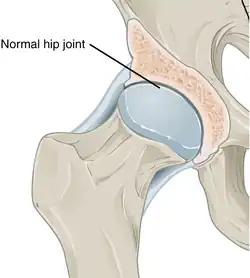

Annotated illustration of healthy hip joint

Healthy hip joint

Annotated illustration of hip joint with osteoarthritis

Hip joint with osteoarthritis[36]

While osteoarthritis is a degenerative joint disease that may cause gross cartilage loss and morphological damage to other joint tissues, more subtle biochemical changes occur in the earliest stages of osteoarthritis progression. The water content of healthy cartilage is finely balanced by compressive force driving water out and hydrostatic and osmotic pressure drawing water in.[37][38] Collagen fibres exert the compressive force, whereas the Gibbs–Donnan effect and cartilage proteoglycans create osmotic pressure which tends to draw water in.[38]

However, during the onset of osteoarthritis, the collagen matrix becomes more disorganized, and there is a decrease in proteoglycan content within cartilage. The breakdown of collagen fibers results in a net increase in water content.[39][40][41][42][43] This increase occurs because whilst there is an overall loss of proteoglycans (and thus a decreased osmotic pull),[40][44] it is outweighed by a loss of collagen.[38][44]

Other structures within the joint can also be affected.[45] The ligaments within the joint become thickened and fibrotic, and the menisci can become damaged and wear away.[46] Menisci can be completely absent by the time a person undergoes a joint replacement. New bone outgrowths, called "spurs" or osteophytes, can form on the margins of the joints, possibly in an attempt to improve the congruence of the articular cartilage surfaces in the absence of the menisci. The subchondral bone volume increases and becomes less mineralized (hypo mineralization).[47] All these changes can cause problems functioning. The pain in an osteoarthritic joint has been related to thickened synovium[48] and to subchondral bone lesions.[49]